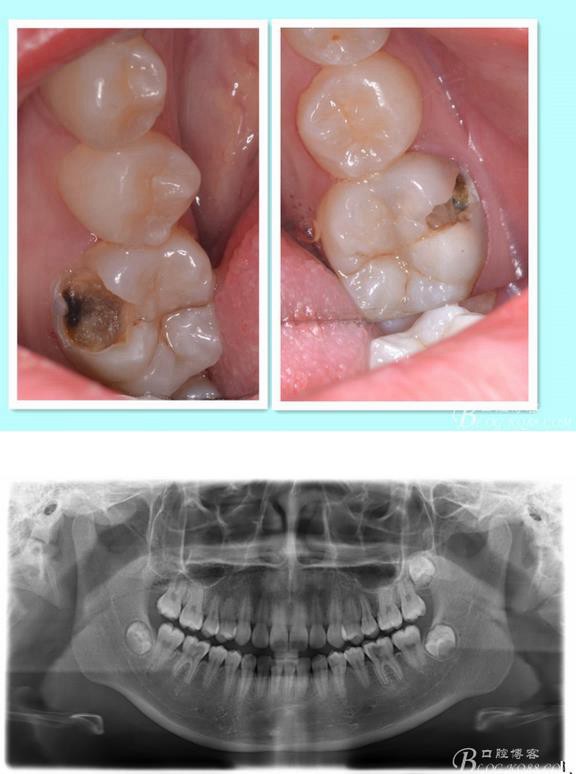

主訴:雙側(cè)下后牙疼痛一月余

病史:近一個(gè)月雙側(cè)下后牙疼痛,自發(fā)性 陣發(fā)性鈍痛,進(jìn)食嵌塞加重,求診

查:雙側(cè)下6頰HE面齲壞 探診疼痛 冷熱刺激 遲反應(yīng)疼痛 叩診(-)頰側(cè)齲壞平齦

X線(xiàn):雙側(cè)下6 齲壞已接近髓腔

診斷:雙側(cè)下6 慢性牙髓炎

治療方案:雙側(cè)RCT+CAD-CAM

這里我單做右側(cè)的詳細(xì)步驟